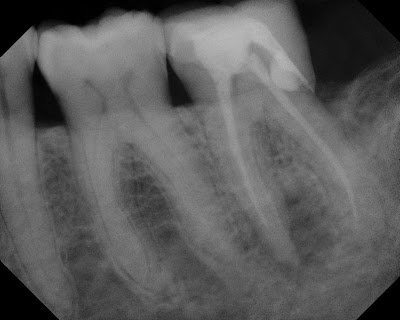

The following example is a root canal that was done 13 months ago by an associate dentist in a general dental practice. This can sometimes create a difficult situation for the owner dentist, when the patient returns with an abscess a year later.

Root canal done 13 months earlier. Large periapical lesion on mesial root. Short root canal filling on mesial canals. The prognosis for this tooth was poor at the time of completion because the MB canal was not cleaned and obturated. Bacterial left behind will continue to cause periapical disease.